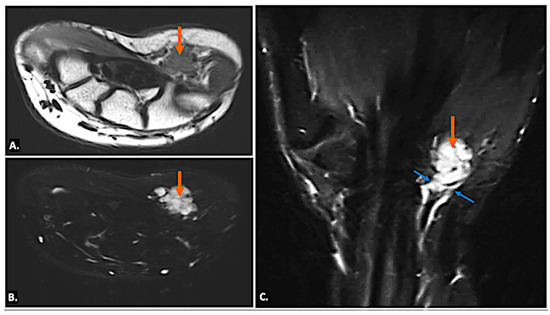

Tenosynovial giant-cell tumours generally arise in relation to the synovial sheath of the tendons or from the synovial lining of the joint. They appear as solid, hypoechoic masses on ultrasound imaging, and the lesions may show well-defined or ill-defined margins. On MRI, they typically appear as low-to-intermediate signal intensity on T1- and T2-weighted images due to hemosiderin deposition and may show blooming on gradient-echo sequences. Post-contrast images reveal variable enhancement (Figure 11). Neurogenic tumours appear as well-defined, hypoechoic masses along the nerve. Doppler imaging may show internal vascularity. On MRI, these lesions are isointense to hypointense on T1-weighted images and hyperintense on T2-weighted images, with a variable presence of “target” appearance on T2, and may show heterogeneous enhancement (Figure 12). The lesions are seen along the course of the ulnar nerve, with the nerve entering into and exiting from it [19].

Figure 11.

(A) Gray-scale Axial Ultrasound image showing a well-defined hypoechoic lesion in the region of Guyon’s canal (indicated by callipers). (B) T1-weighted and (C) T2-weighted axial MR images of the same case showing a well-defined lobulated lesion (arrow) appearing iso-to-hypointense to muscle on both (B) T1-weighted and (C) T2-weighted axial MR sequences in keeping with a tenosynovial giant-cell tumour.

Figure 12.

(A) T2-weighted, fat-suppressed coronal and (B) T2-weighted, fat-suppressed axial MR images of a neurogenic tumour showing a well-defined elongated lesion (arrow) along the course of the ulnar nerve appearing hyperintense on T2-weighted, fat-suppressed coronal (A) and demonstrating ‘Target-Sign’ with central hypointense signal on axial T2-weighted, fat-suppressed (B) sequences.